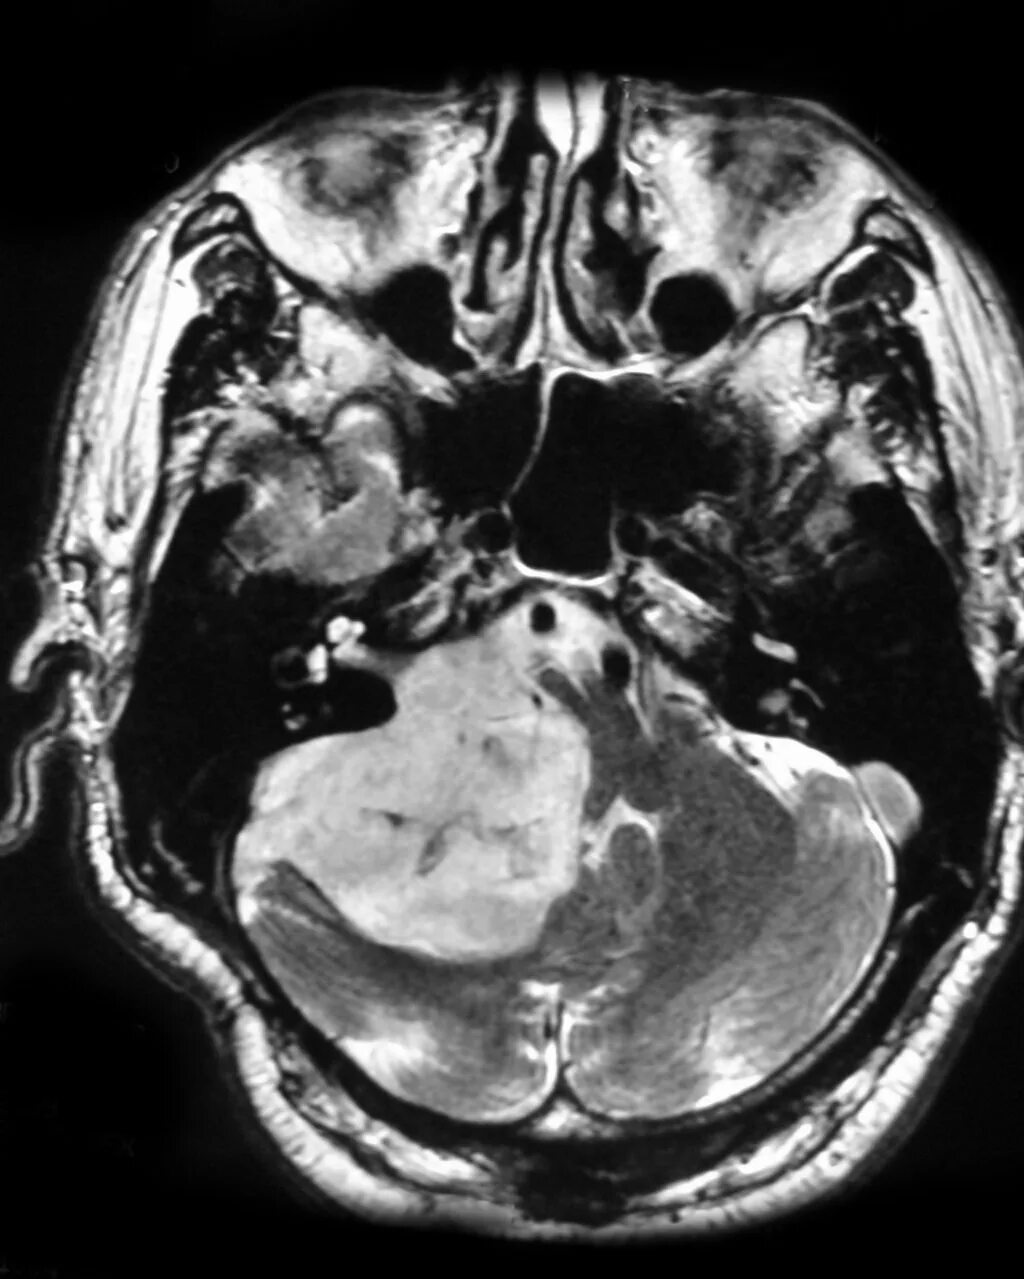

Мрт головного мозга мосто мозжечкового угла